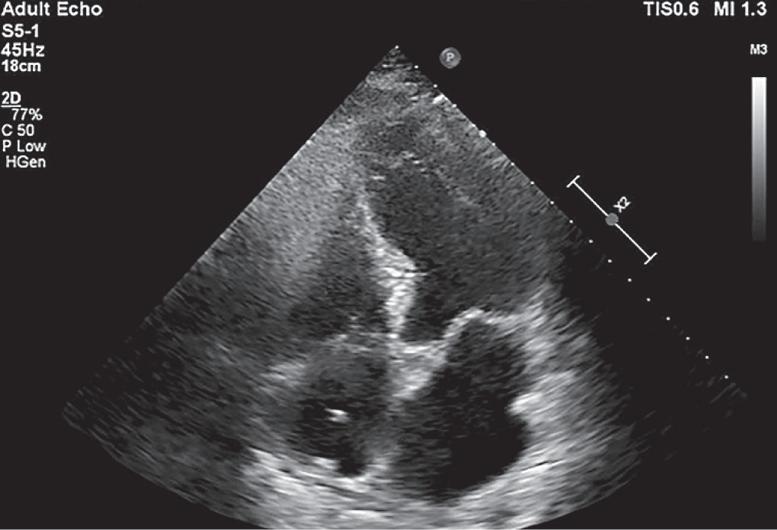

Em um cateter venoso, promove-se a infusão de 10mL de uma solução de glicose agitada com monitorização ultrassonográfica simultânea das cavidades cardíacas direitas: átrio e ventrículo. Estando o cateter localizado no sistema venoso, haverá a chegada dessa solução, que forma um “contraste” (microbolhas agitadas), primeiramente nessas câmaras, confirmando a localização do cateter no sistema de vasos venosos (Figuras 1.3 e 1.4).7

fIGU r A 1.4 Cateter venoso central (CvC) no interior do átrio direito (seta)

ad: átrio direito; vd: ventrículo direito; ae: átrio esquerdo; ve: ventrículo esquerdo .

Fonte: arquivo pessoal dos autores